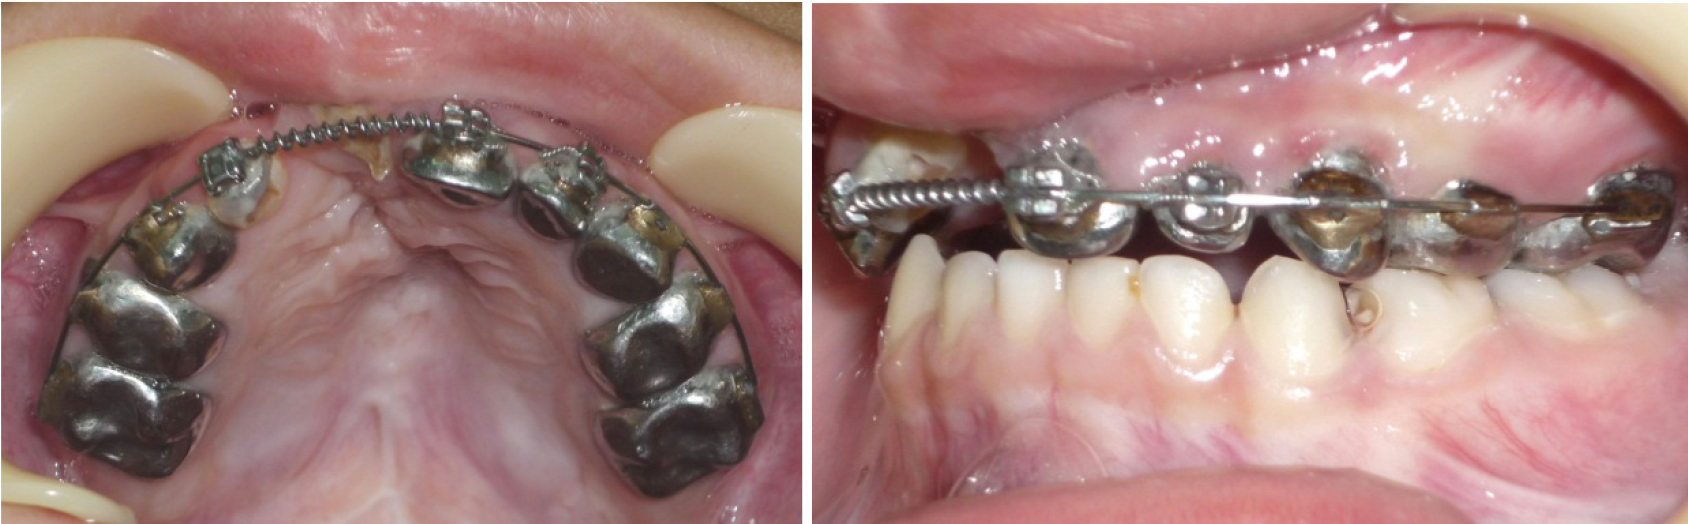

Лечение проводилось с применением несъемной дуговой аппаратуры. Фиксирующими элементами служили тонкостенные коронки (кольца) с припаянными вестибулярными брекетами. Размер металлической дуги определяли с помощью предложенных методов графического анализа (рис. 3). Металлические дуги меняли с учетом протокола лечения эджуайс-техникой до нормализации формы арки, соответствующей прогнозируемым размерам. После нормализации окклюзионных взаимоотношений аппарат использовался в качестве ретенционного до смены молочных зубов постоянными (рис. 4).

Анализ данных биометрии показал, что на стороне расщелины расстояние от условной сагиттали до молочного клыка составляло до лечения (11,52 ± 0,93) мм, а после лечения исследуемый параметр составлял (16,39 ± 0,64) мм (р ˂ 0,05). На котрлатеральной стороне разница в изменении положения клыка была не достоверной и в динамике лечения изменялась с (14,93 ± 0,79) до (16,27 ± 0,84) мм (р ˃ 0,05). Отмечалось изменение размеров диагоналей переднего сектора дентальных арок (клыковых диагоналей), которые на стороне расщелины в динамике изменялись от (13,34 ± 0,96) до (18,27 ± 0,71) мм (р ˂ 0,05). На контрлатеральной стороне исследуемый показатель изменялся с (16,73 ± 0,87) до (18,12 ± 0,95) мм (р ˃ 0,05). Диагонали зубных дуг (центрально-молярные) с обеих сторон после лечения составляли по (35,52 ± 1,13) мм.